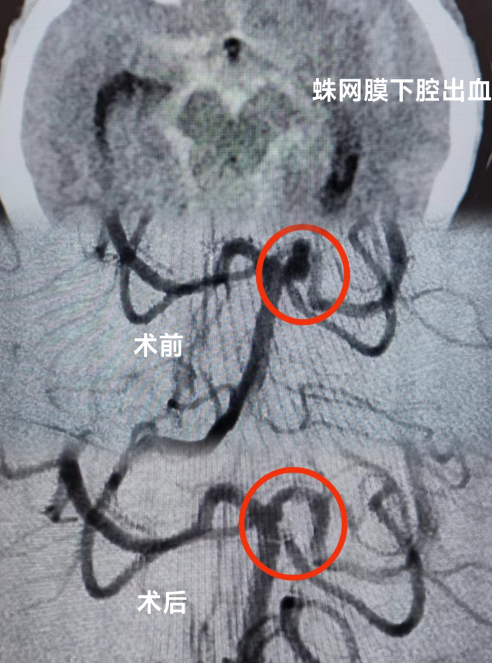

当天,患者被送到急诊科时,医生为她紧急安排头颅CT检查,发现患者有蛛网膜下腔出血的情况。蛛网膜下腔出血通常病情比较严重,可诱发脑血管痉挛,进而继发出现脑梗死,危害患者生命。为了帮助患者尽快脱离危险,急诊科立即联系了神经外科、重症医学科及心血管内科当班医生进行联合会诊。

我院多学科专家团队结合患者检查结果,认真分析患者病情,判断患者动脉瘤破裂出血可能性大,同时合并有急性冠脉综合征,不排除急性心梗的可能。考虑到患者病情的危重性及复杂性,专家团队建议患者入住重症监护病房(ICU),紧接着由神经外科医师团队运用神经介入技术为患者进行脑血管疾病诊治,同时神经外科医师与心血管内科介入医师通力合作,排查了心脏冠脉相关疾病。期间,麻醉科、重症医学科医师团队也全程为患者保驾护航,排查手术各种风险。

手术历经约3个小时,专家团队排除万难,为患者完成了全脑血管、冠脉造影术,以及颅内动脉瘤介入栓塞术手术,术后患者恢复良好。